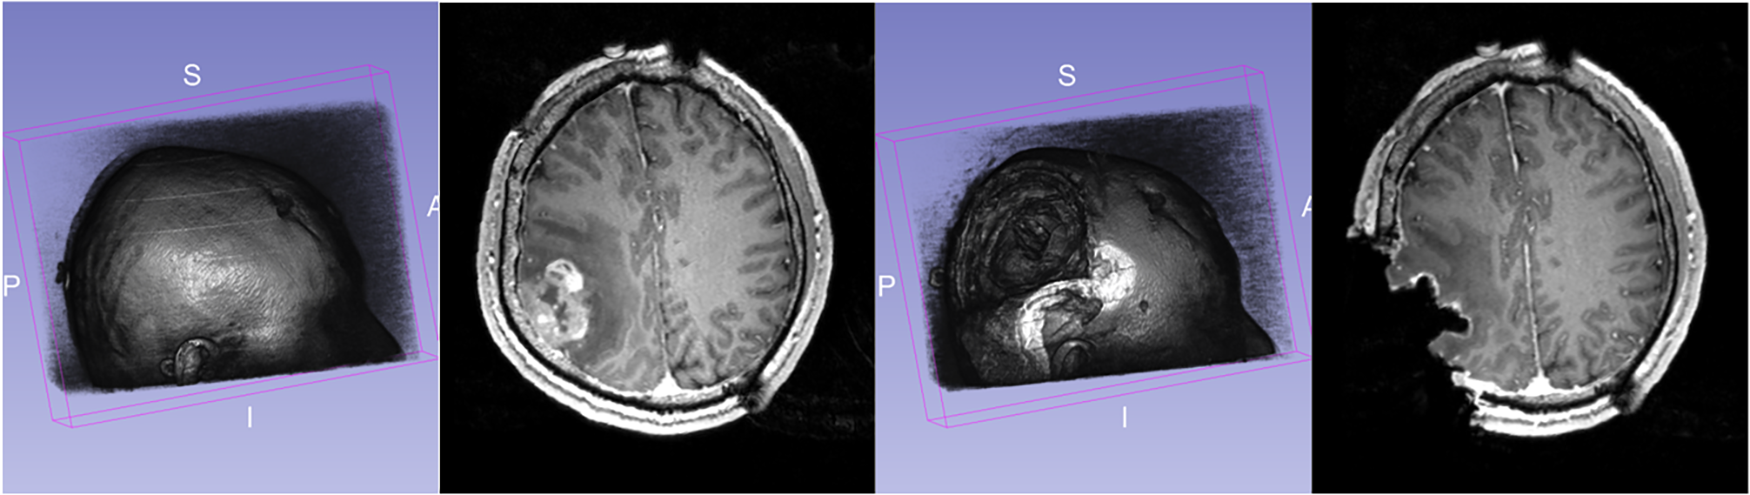

During surgery, the opening of the skull and dura causes changes in pressure inside the Intra-Cranial Cavity. Because of this and other factors, such as cerebrospinal fluid drainage and gravity's effect, the brain changes its shape, introducing discrepancies in relation to the pre-operative configuration. The adoption of intraoperative MRI (iMRI) has provided a means for monitoring brain deformation (or brain shift) during surgery (6). Figure 1 depicts the preoperative and interoperative MRI data before and during brain tumor resection. The number of hospitals offering iMRI has grown over the past decade from a handful of research centers to hundreds of clinical sites worldwide (7). Although acquiring fMRI and DTI during surgery may not be feasible, the preoperative images can be aligned with an iMRI through non-rigid registration. The registration results could be applied to preoperative fMRI and DTI, offering more accurate and updated guidance to the neurosurgeon (8). Deformable transformation use on fMRI and DTI is beyond the scope of this paper. This study evaluates deformable registration accuracy between pre-op MRI and intra-op MRI.

Figure 1

Discrepancies between preoperative and intraoperative MRI before and during neurosurgery: volume rendering and axial view. Preoperative MRI (left) and intraoperative MRI (right) are acquired after a substantial part of the tumor is removed.